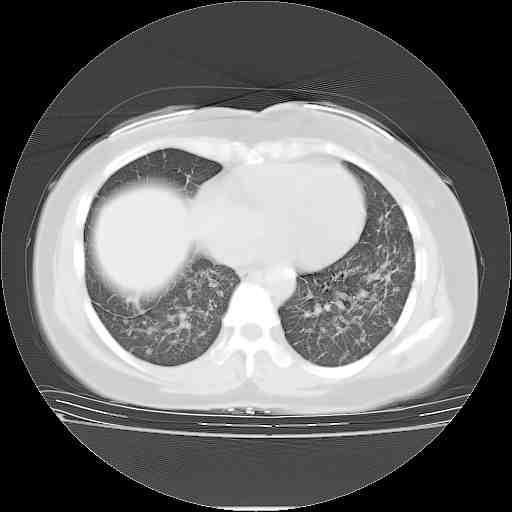

考虑  腺癌肺内转移,治疗较前病灶缩小、减少

肺癌并肺内转移,这种疾病治疗后在影像上看略有好转,不是很显著,但是肿瘤治疗效果影像只是一方面。

支持肺癌并肺内淋巴管炎,  原发灶小了,但转移较前片明显了.

支持右肺下叶周围型肺癌并肺内淋巴管炎,  原发灶小了,但转移较前片明显了.。

标准的细支气管肺泡癌呀!治疗后病情有所控制,也没治愈的迹象!

支持右肺下叶周围型肺癌并肺内淋巴管炎;病灶有所控制。